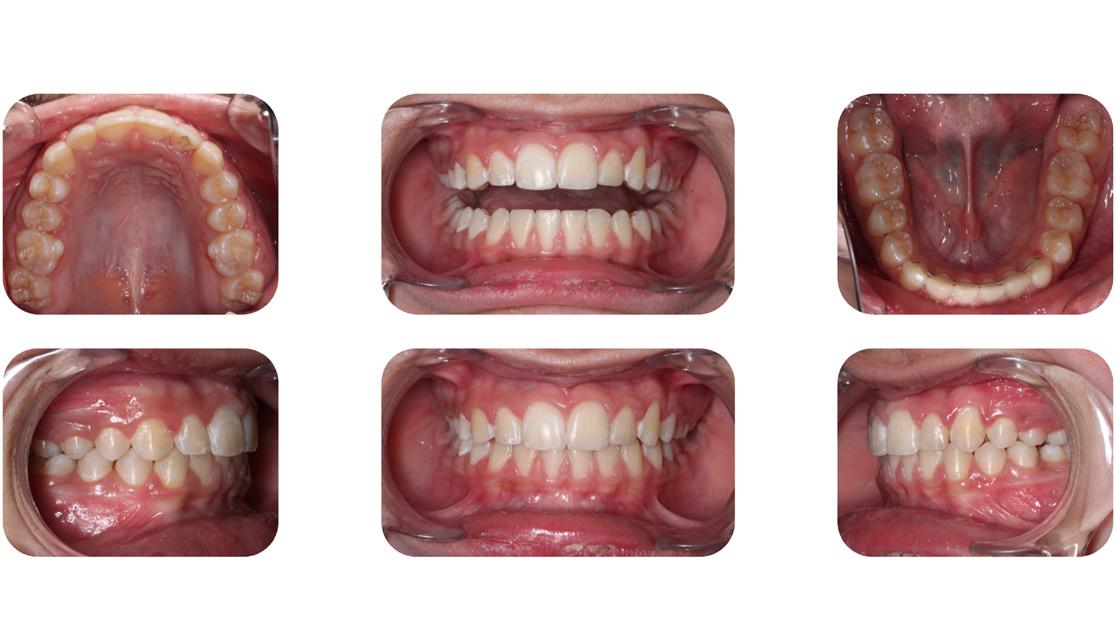

After re-bracketing, the treatment continued with the progression of the arch wires: a .014 NiTi, a .018 NiTi, a .019x025 “V” Force -3 and the final arch wire a .018x.025 SS. These final arch wires were left for three months. After this time, the esthetics, TMJ, airway, occlusion and alignment were evaluated. The patient reported that he was satisfied, and very happy with the result (Figure 11-A, B, C, D, E, F).9

11A: Pre-debracketing, lateral view

11B: Pre-de-bracketing, panoramic radiogram

FIG. 11C: Pre-de-bracketing, lips in repose

FIG. 11D: Pre-debracketing, posed smile

FIG. 11E: Pre-debracketing, right lateral view

FIG. 11F: Pre-debracketing, left lateral view